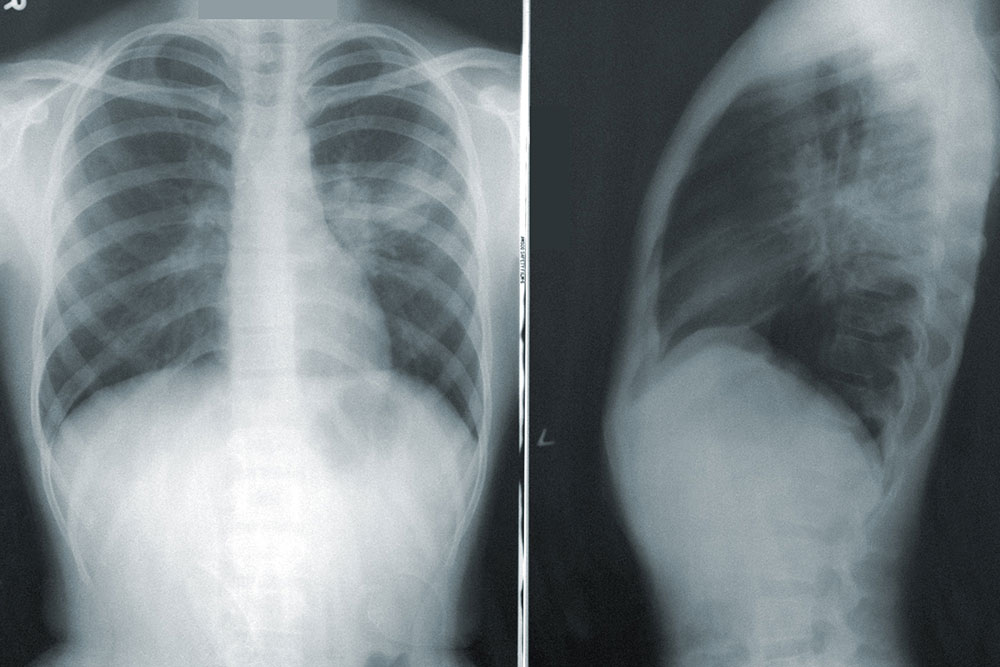

Chest X-Ray

A chest X-ray is a picture of the chest that shows your heart, lungs, airway, blood vessels, and lymph nodes.